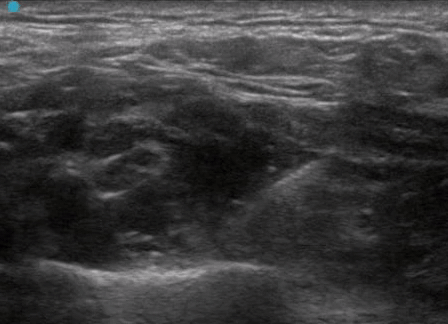

INDICATIONS : deltoid abscess incision and drainage, humeral fracture pain control, elbow dislocation/reduction, distal radius fracture/reduction, etc.

Recommend: use a Blunt Tip block needle and inject with LOW PRESSURE. Always stay away from the nerve if possible. We like using the first rib as a backstop. Anesthetic type and amount should be based on the case (always be aware of maximal dosing).